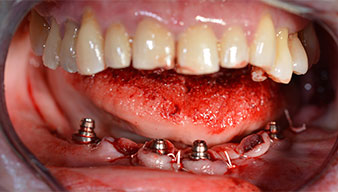

The 64-year-old patient presented with residual dentition of teeth 38, 33 and 43 and a clasp denture in the mandible (Fig. 1 and 2).

Fig. 1

Fig. 2

After removal of the residual dentition in the mandible, the alveolar crest was exposed from 37 to 47.

The mental foramen was first identified as a limiting anatomical structure and then the cortical bone of the crest was smoothed with the straight handpiece and a large rose-head bur (Fig. 4).